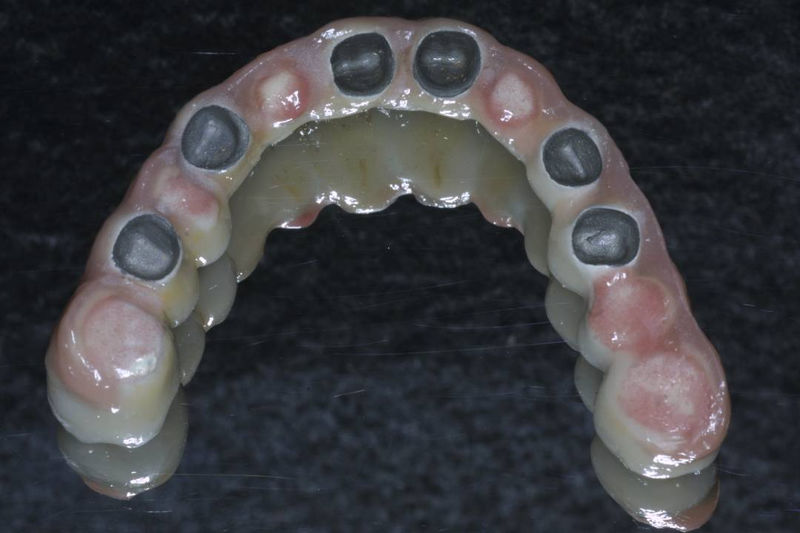

Restauraciones fabricadas en el laboratorio los cuales se usan para reemplazar dientes ausentes en toda una arcada usando implantes y/o tejidos blandos como soporte y que pueden y deben de ser removidas para su limpieza. Para poder enviar el caso al laboratorio se toman impresiones utilizando materiales de impresión o técnicas modernas digitales.